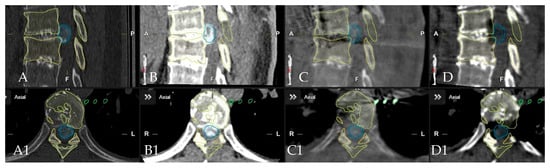

Surgical Treatment of Calcified Thoracic Herniated Disc Disease via the Transthoracic Approach with the Use of Intraoperative Computed Tomography (iCT) and Microscope-Based Augmented Reality (AR)

4. Patients

5.1. Surgical Technique and Outcome for Resection of Calcified Thoracic Disc

5.2. Anterolateral vs. Posterior Approach and Analysis of Clinical Outcomes

5.3. Use of Navigation and Intraoperative Imaging in the Resection of Herniated Thoracic Discs

5.4. Applications of Augmented Reality for Degenerative Spine Surgery